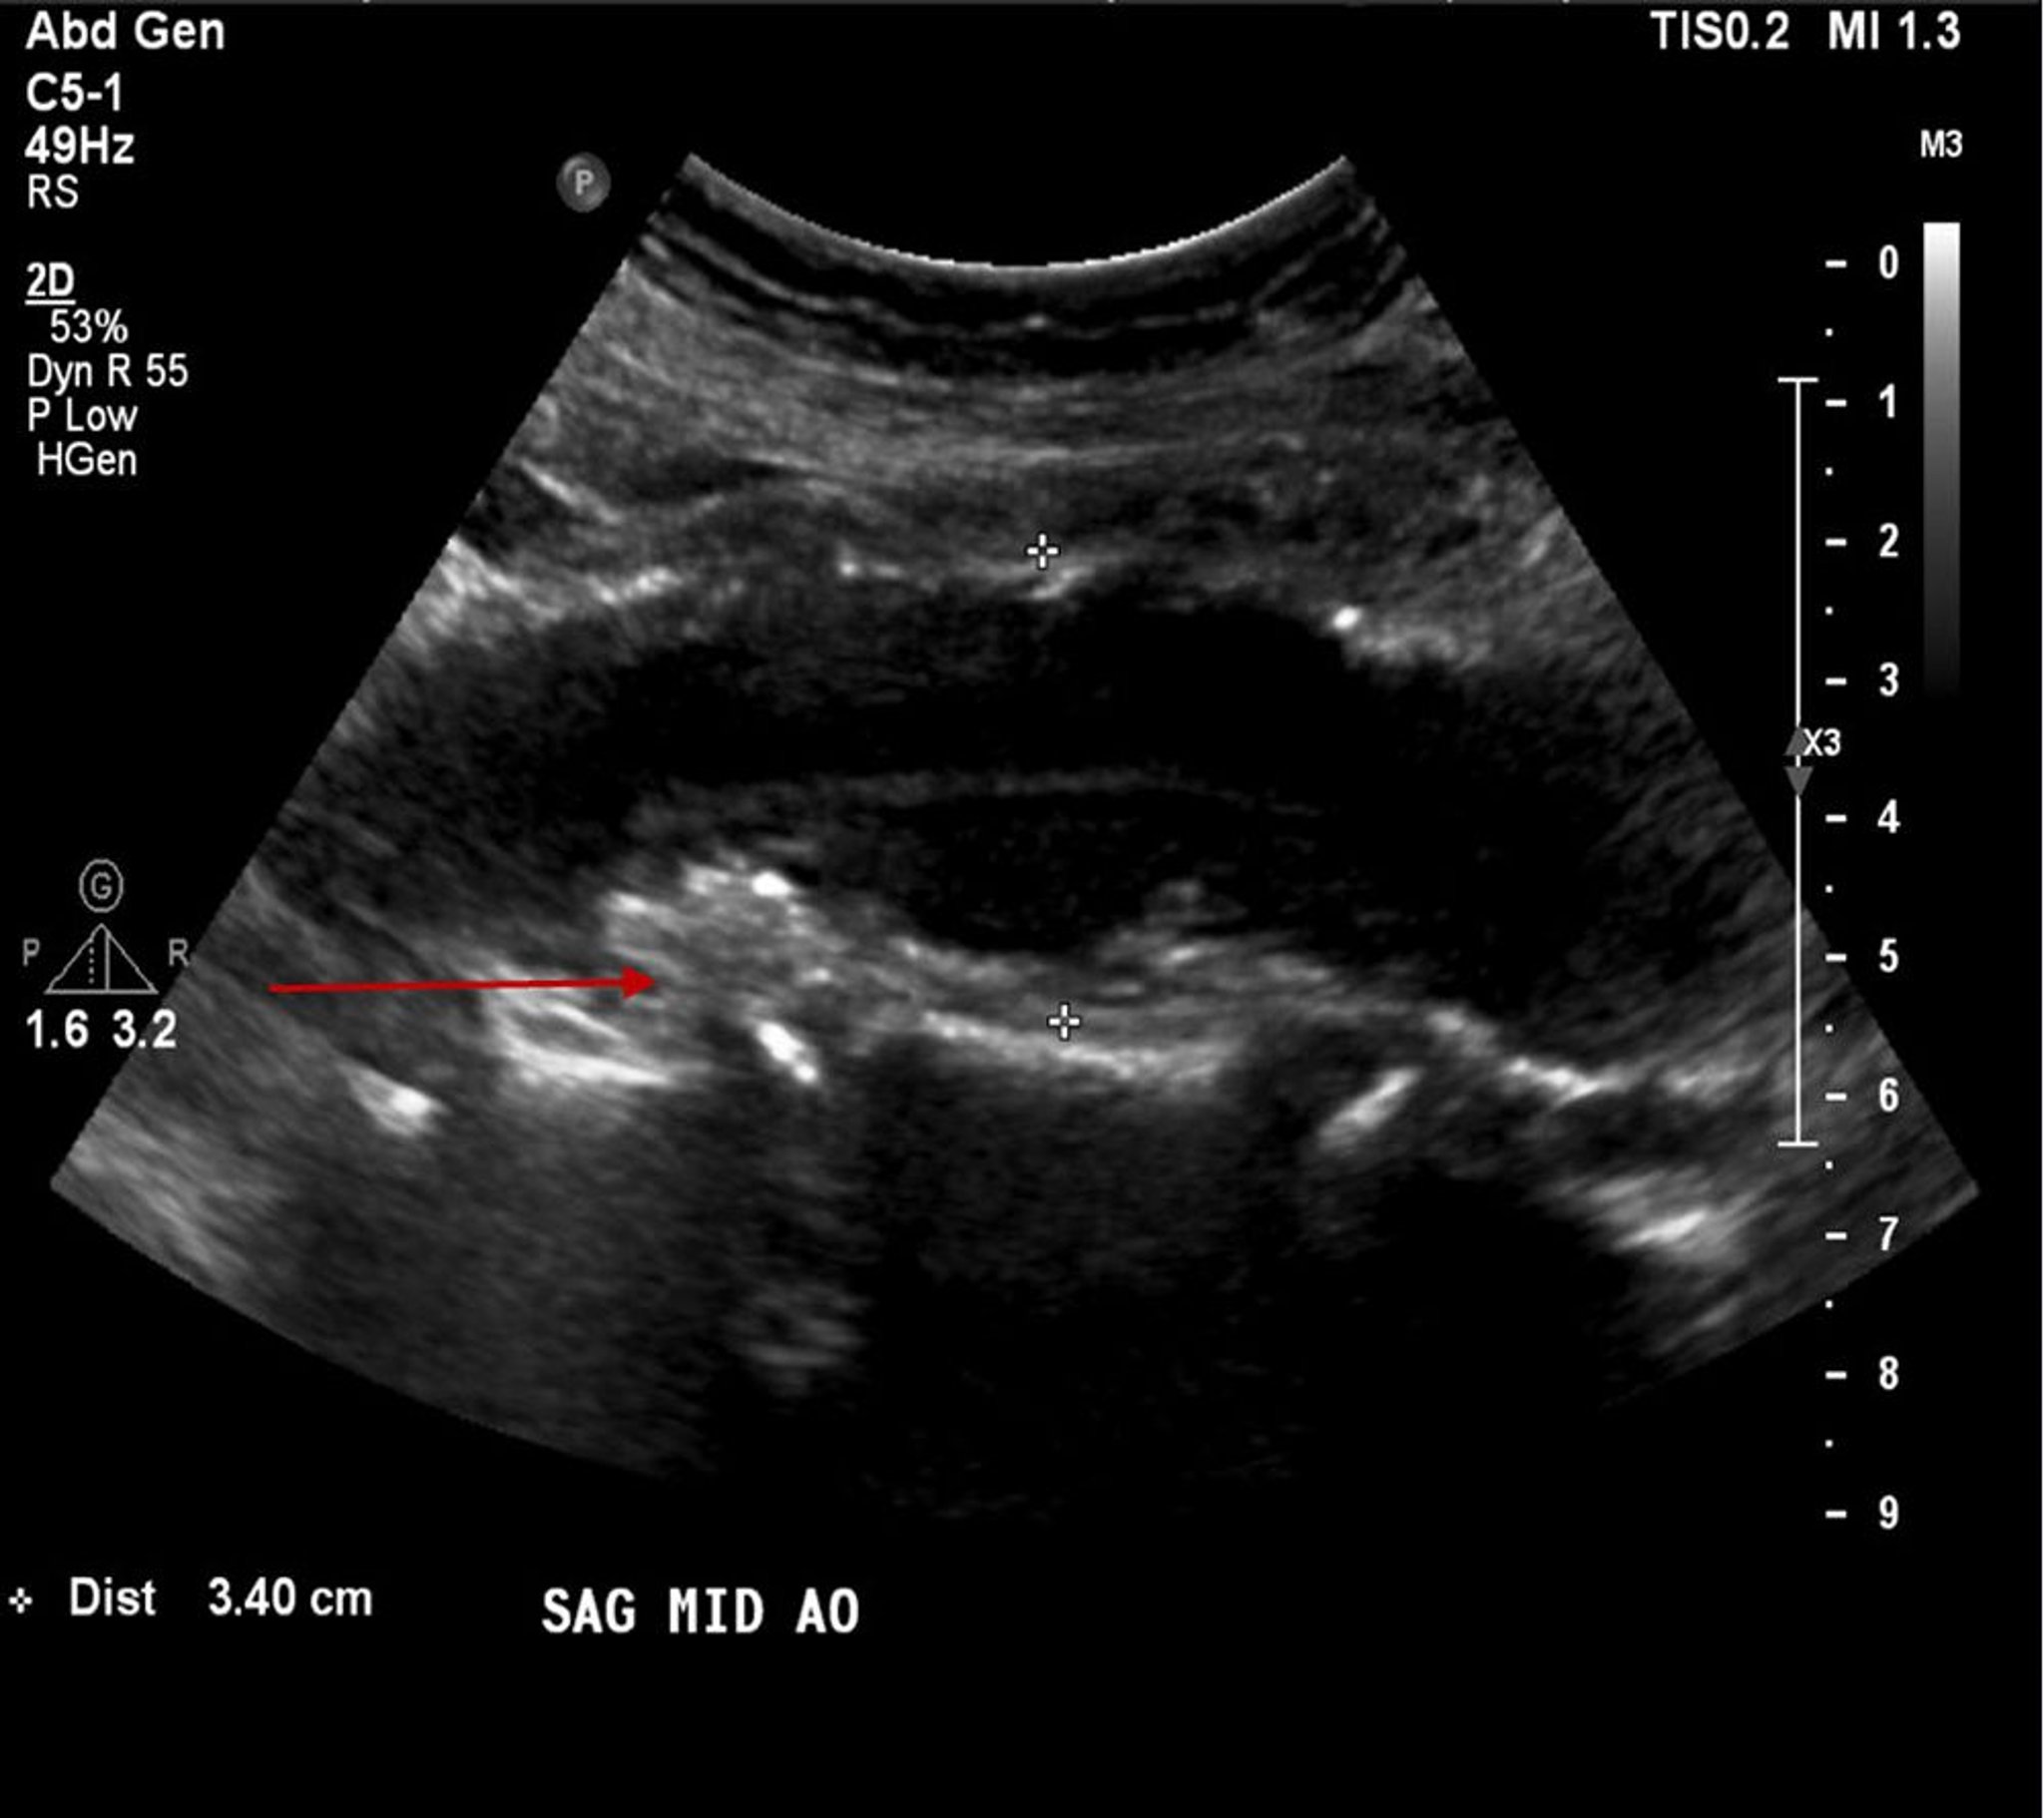

Anévrisme de l'aorte abdominale (échographie)

Ce patient a un anévrisme de l'aorte abdominale mesurant 3,4 cm ainsi (entre les croix blanches) qu'une plaque athéroscléreuse ou un thrombus mural (flèche rouge).